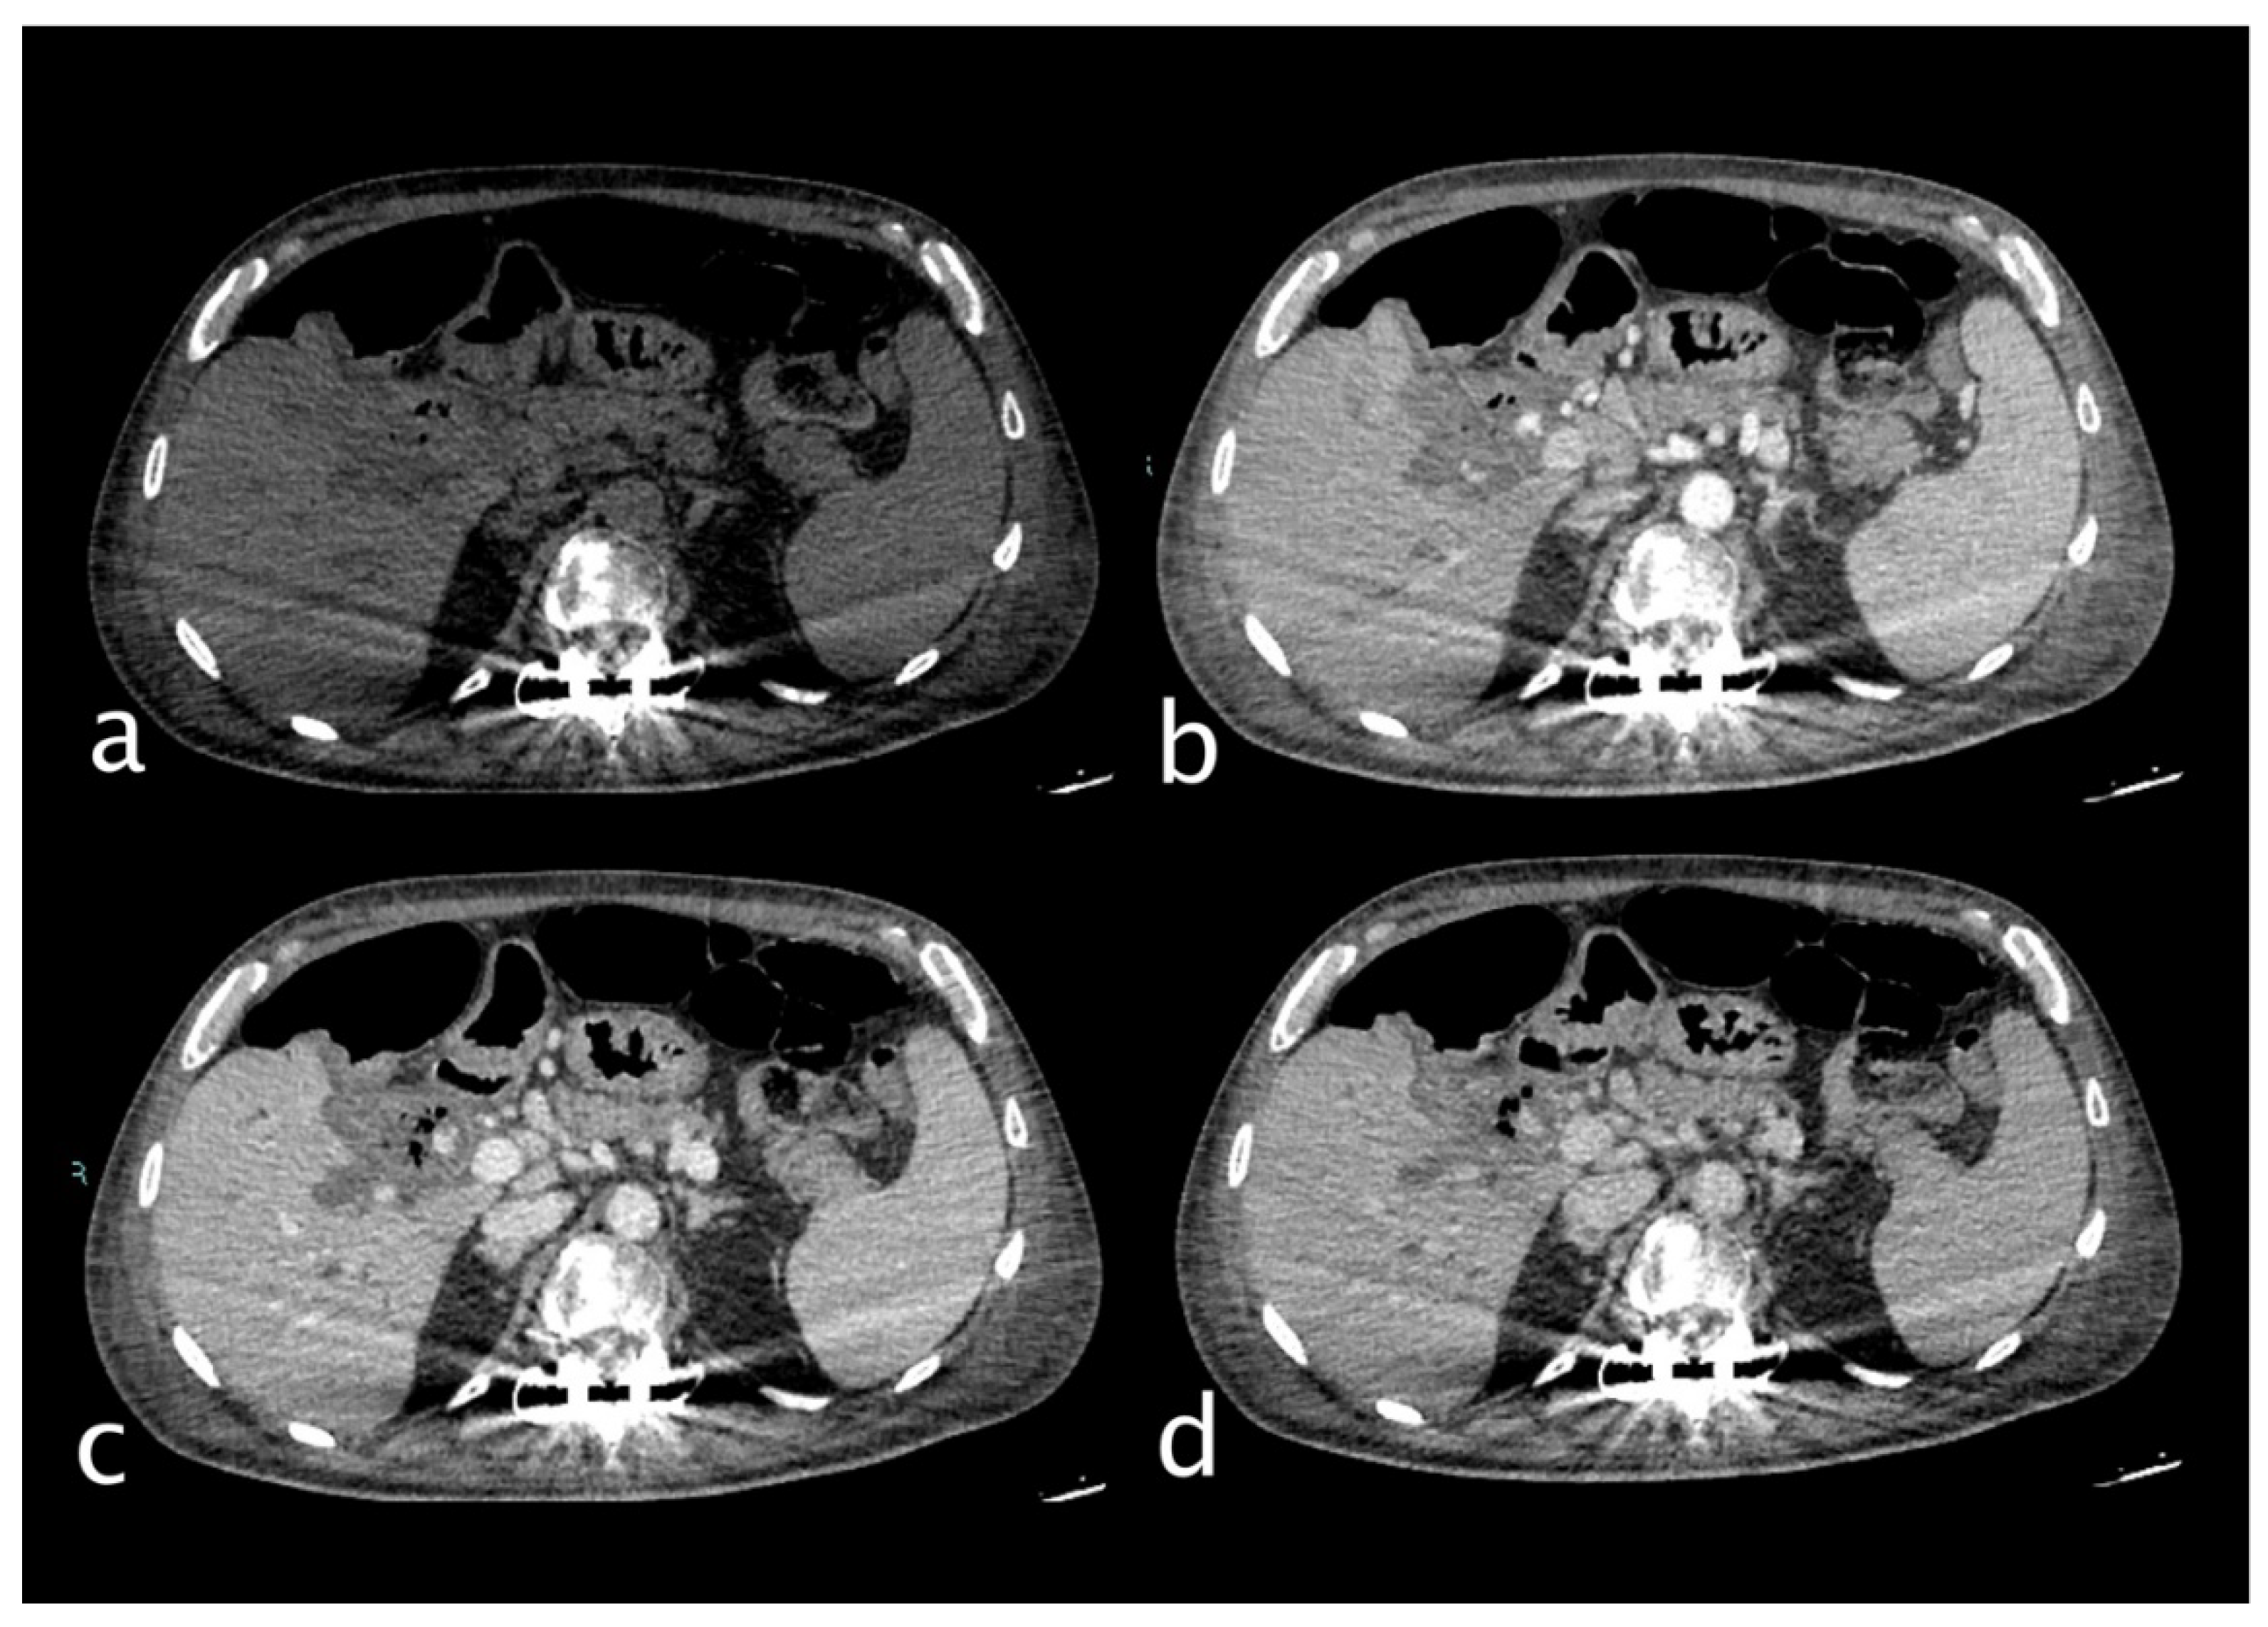

Figure 3.

Hemodynamically stable 30 years old male who underwent MVA trauma (Hb 11,9 g/dl, n.v. 13-18; PCR 0,43 mg/dl, n.v. 0.0-0.5; WBC 15,19 103/mm3 n.v. 4.2-10.5). He underwent CT with IV contrast (a non-contrast, b arterial, c venous, d delayed phase) that showed subcapsular and pericholecystic hematoma, laceration with non-active bleeding of the fourth hepatic segment and cystic artery active bleeding (a,white arrow) along the anterior gallbladder profile with conspicuous increase of contrast extravasation in portal (c)and delayed (d) phases.